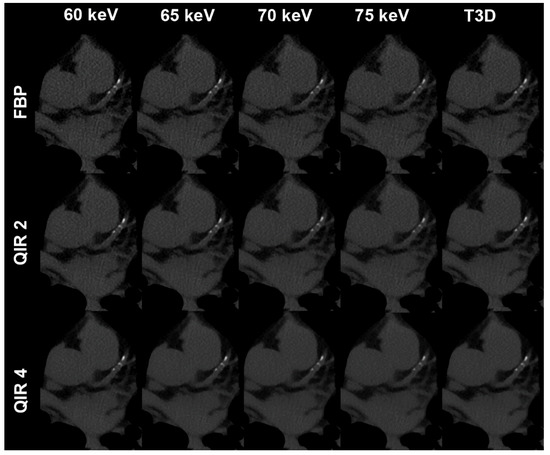

| VMI/T3D | FBP/no QIR | QIR 1 | QIR 2 | QIR 3 | QIR 4 |

|---|---|---|---|---|---|

| 60 keV | 107 (48–1060) | 100 (44–1026) | 91 (40–999) | 86 (36–974) | 80 (33–952) |

| 65 keV | 105 (44–1024) | 98 (40–989) | 90 (36–957) | 82 (33–930) | 74 (30–896) |

| 70 keV | 86 (38–978) | 76 (35–939) | 65 (31–886) | 64 (27–877) | 59 (24–850) |

| 75 keV | 64 (29–895) | 59 (26–867) | 56 (23–839) | 53 (21–819) | 49 (20–803) |

| T3D | 101 (46–1035) | 95 (43–1013) | 86 (39–981) | 80 (37–959) | 76 (34–934) |